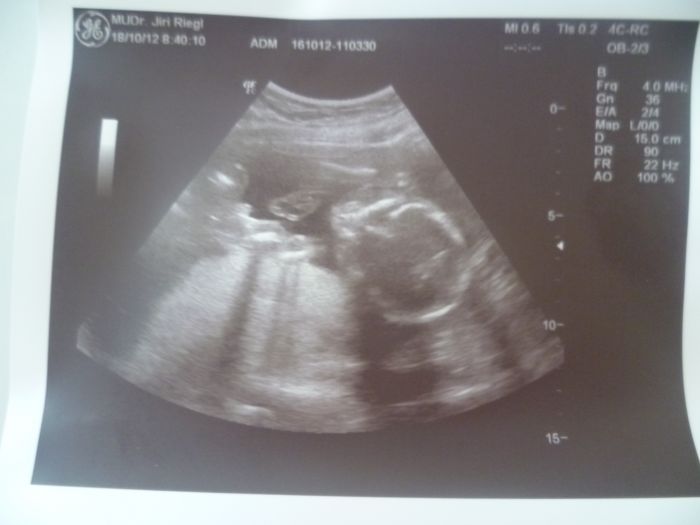

. Ale napsali jste to holky hezky, musíte dál bojovat

a jestli vám to nevadí, tak vám sem na povzbuzení dám fotečku z dnešní poradny, jsem 21.t., pokud to některé vadí, tak se omlouvám